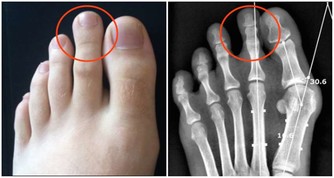

長期過量吃糖,會帶來這些危害:傷牙、長胖、跟骨頭搶鈣、加速皮膚老化、誘發多種疾病(痛風、糖尿病、心腦血管等慢性病)。